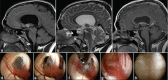

Background: Colloid cysts are usually located at the rostral part of the third ventricle in proximity to the foramina of Monro. Some third ventricular colloid cysts, however, attain large sizes, reach a very high distance above the roof of the third ventricle, and pose some challenges during endoscopic excision. These features led to the speculation that for such a pattern of growth to take place, the points of origin of these cysts should be at areas away from the foramina of Monro at which some anatomical "windows" exist that are devoid of compact, closely apposed forniceal structures.

Results: Colloid cysts may grow vertically up past the roof of the third ventricle through anatomical windows devoid of the mechanical restraint of the forniceal structures.

Conclusion: Some anatomical variations of the forniceal structures may allow unusually large sizes and superior vector of growth of a retro- or post-foraminal colloid cyst. Careful preoperative planning and knowledge of the pertinent pathoanatomy of these cysts before endoscopic excision is very important to avoid complications.